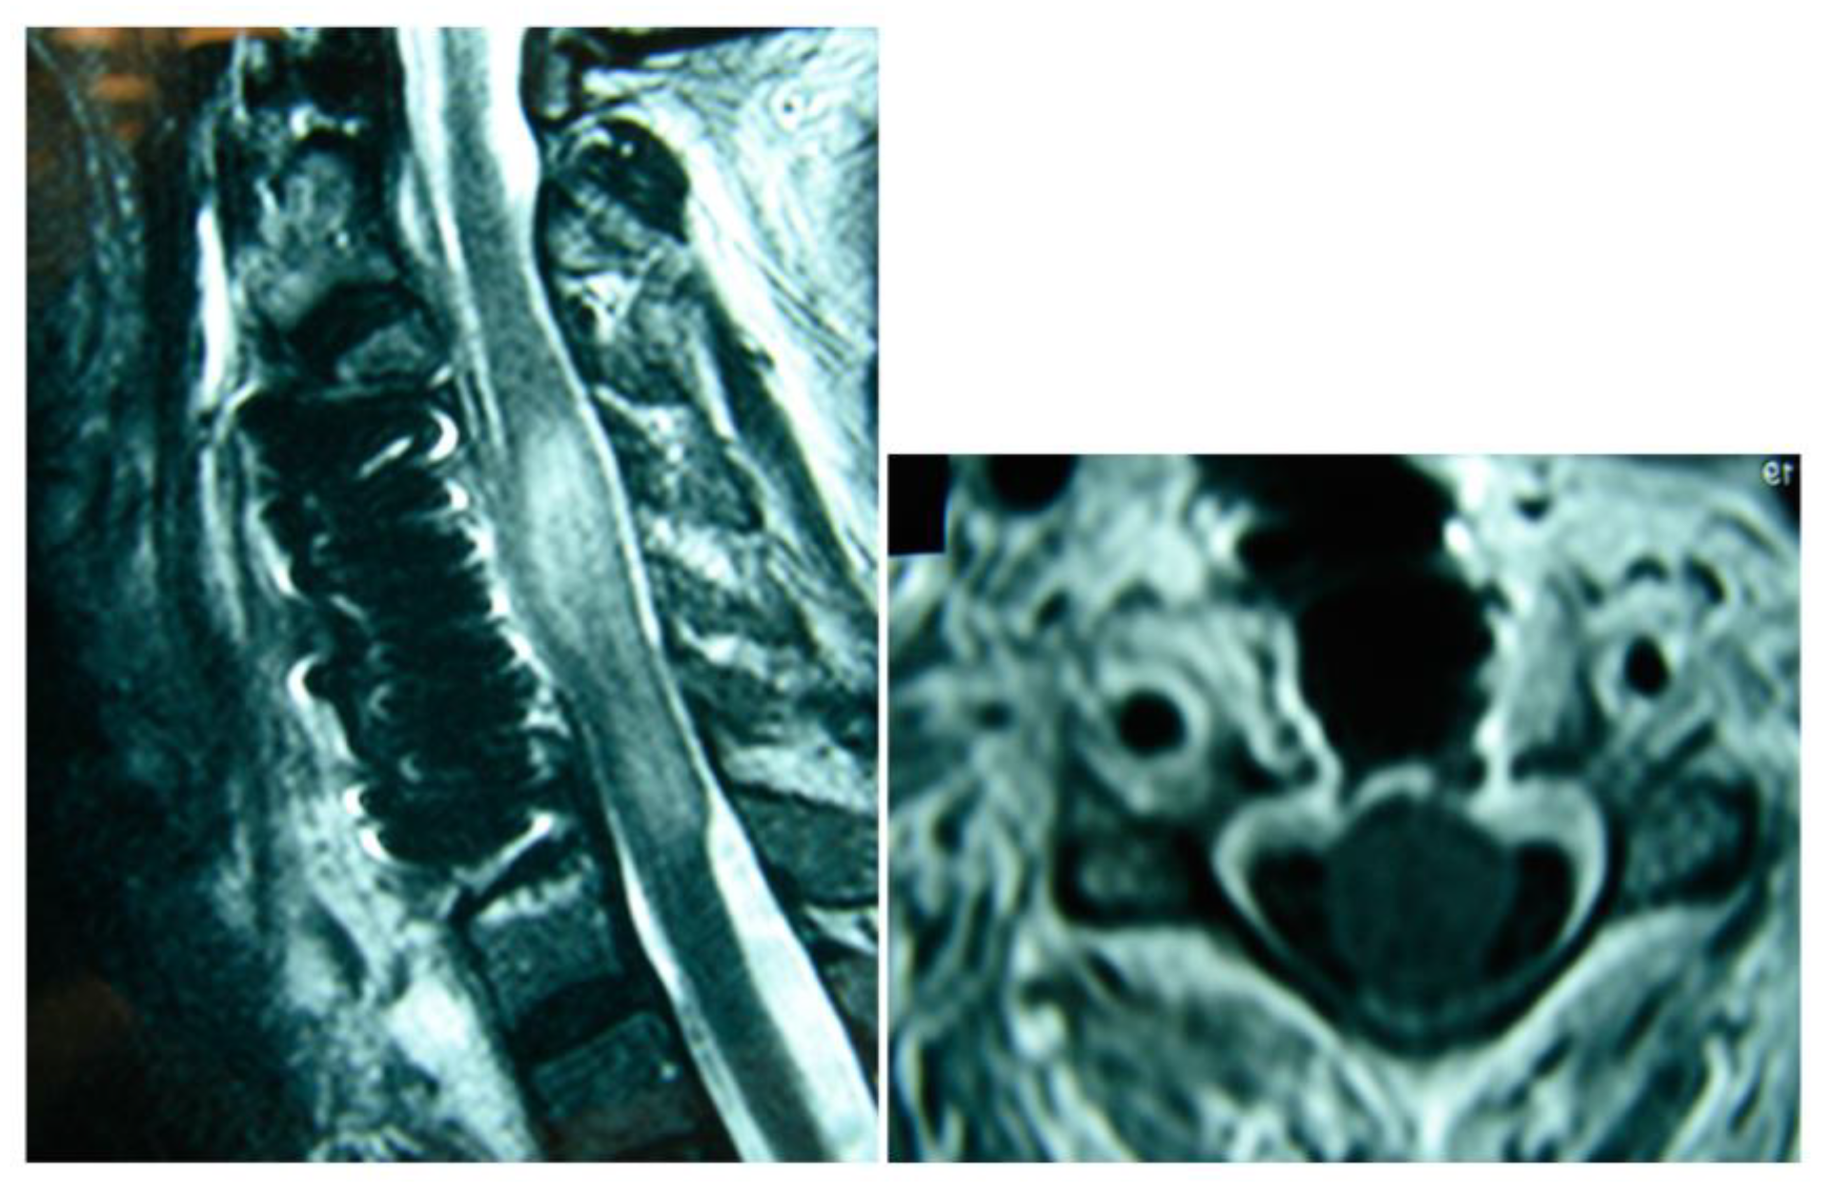

| 1 | 23 | M | C2–C4 | Staphylococcus aureus | Debridement and fusion | Fever, pain, numbness, and muscle weakness bilaterally | Full recovery, dysphagia for 2 weeks postop | Abuse of venous drugs |

| 2 | 68 | M | C2–C4 | Staphylococcus aureus | Debridement and fusion | Fever, pain, numbness, and muscle weakness bilaterally | Full recovery | Diabetes mellitus |

| 3 | 56 | F | C1–C5 | Staphylococcus aureus | Debridement and fusion | Fever, pain, numbness, and muscle weakness bilaterally | Full recovery 2 years post op, muscle weakness | |

| 4 | 69 | M | C2–C5 | Staphylococcus aureus | Debridement and fusion | Incidentally upon spinal imaging | Full recovery, dysphagia for 2 weeks postop |